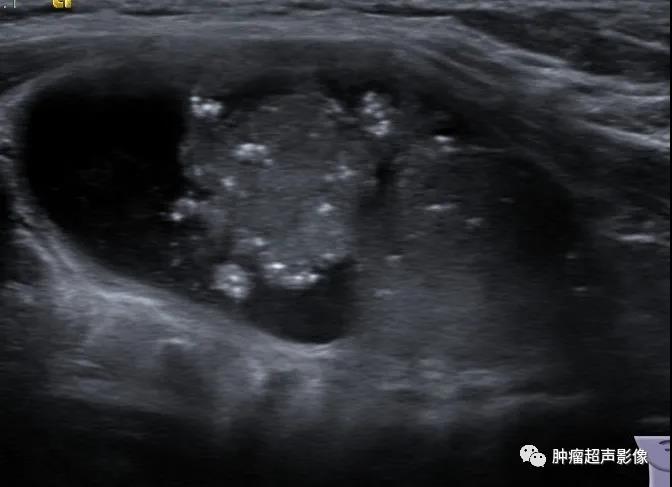

1、微钙化:与实性甲状腺乳头状癌相同,实性部分的微钙化对甲状腺囊性乳头状癌的诊断具有极高特异性(被部分学者描述为“海岛珍珠征”)。

来自微信会诊病例:形态不规则,微钙化,实性部分向周边的壁伸出多个较细的分隔(“蜘蛛征”),血流由中心向四周发出的分支动脉血流(“烟花征”)符合典型囊性乳头状癌,术后病理证实为乳头状癌